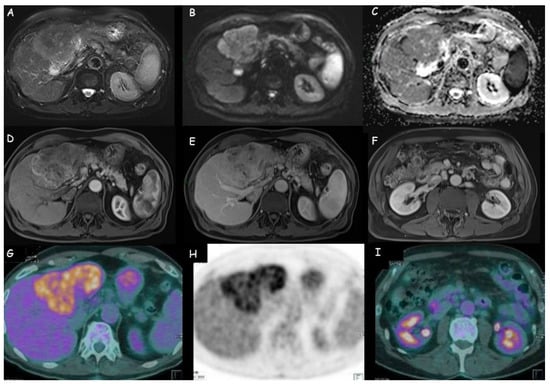

Figure 3.

Magnetic resonance imaging of a 3 cm intrahepatic cholangiocarcinoma in segment III: (A,B) Moderately hyperintense lesion in T2 weighted sequences with weak restriction in diffusion-weighted imaging; (C,D) Peripheral contrast enhancement with perfusional alterations.

Figure 4.

(A–E) Magnetic resonance imaging of an intrahepatic cholangiocarcinoma of 11 cm × 7 cm in the left liver lobe: weak hyperdensity in T2 weighted sequences; restriction at diffusion-weighted imaging (DWI); peripheral wash-in with late central retention. (F) Lymphadenopathies in celiac, hepatic, and left paraaortic area. (G,H) Positron emission tomography with 18-fluoro-2-deoxy-d-glucose (18FDG-PET) of the same lesion: increased uptake of the metabolic agent in the hepatic hypodense lesion, with markedly inhomogeneous distribution of the radiopharmaceutical. (I) Weak uptake of the metabolic tracer in the locoregional lymph nodes.